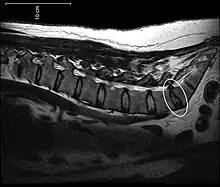

Disc protrusion

[1] A disc protrusion is a medical condition that can occur in some vertebrates, including humans, in which the outermost layers of the anulus fibrosus of the intervertebral discs of the spine are intact but bulge when one or more of the discs are under pressure.

A disc protrusion may progress to a spinal disc herniation, a condition in which there is a tear in the anulus fibrosus.[2] The most common area to have a disc protrusion is in the Lumbar Spine, specifically L-5.[2]